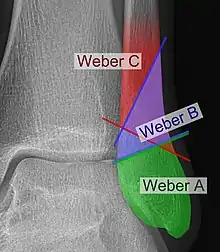

The Danis–Weber classification (often known just as the Weber classification) is a method of describing ankle fractures. It has three categories:[1]

Fracture of the fibula distal to the syndesmosis (the connection between the distal ends of the tibia and fibula). Typical features:

Fracture of the fibula at the level of the syndesmosis. Typical features:

Fracture of the fibula proximal to the syndesmosis. Typical features: